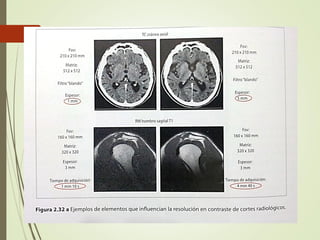

RESOLUCION EN CONTRASTE:

Es la capacidad de distinguir a simple vista dos objetos de

intensidad próxima.

Influencian esto:

• Relación S/R

• Cuantificación

• Ventaneo

En TAC se usan filtros blandos para optimizar el estudio en

Resolución espacial:

Se define como la distancia mínima que permite

distinguir dos objetos de fuerte intensidad.

La RE se expresa bajo forma de frecuencia en

“números de ciclo” por unidad de distancia. (ej.

pL/MM)

En Dx digital depende :

• Cadena de detección

• Tamaño del pixel

• Muestreo